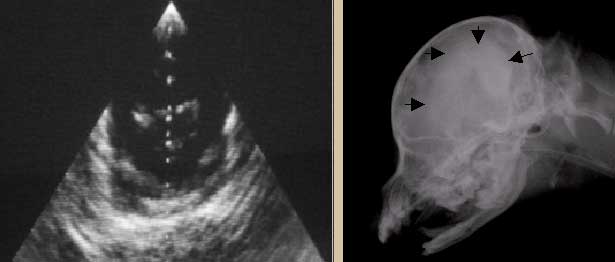

Диагноз гидроцефалия ставят на основании типичной клинической симптоматики, ультразвуковой визуализации расширенных боковых желудочков мозга, контрастной энцефалографии, компьютерной томографии или магнитно-резонансной томографии.

Увеличение боковых мозговых желудочков при УЗИ и контрастной энцефалографии (контрастная тень в форме «земляного ореха»).